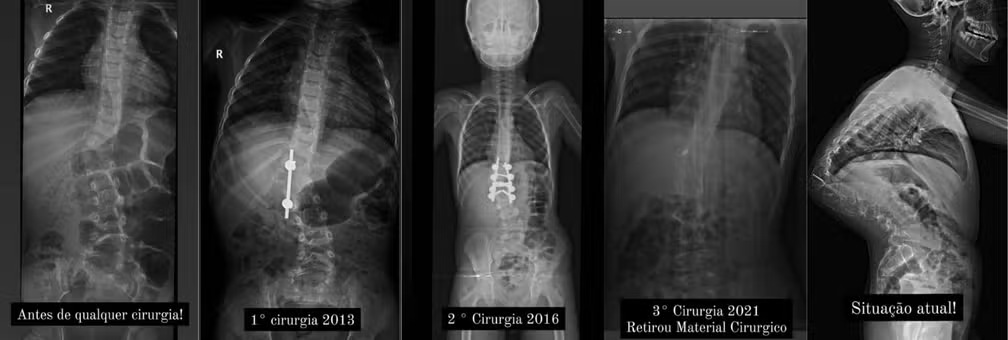

Menino com curvatura de 127º na coluna já realizou três cirurgias — Foto: Arquivo Pessoal

Murilo Arruda, um adolescente de 15 anos da cidade de Lupércio, interior de São Paulo, passou por uma cirurgia de correção de cifoescoliose congênita, uma condição que envolve desvios posterior e lateral na coluna vertebral. Com uma curvatura de 127 graus na coluna, Murilo enfrentava compressão de órgãos vitais como o pulmão e o coração, desde o nascimento. Relembre o caso.

A comoção gerada pela história de Murilo resultou em apoio e solidariedade, culminando finalmente na realização da cirurgia pelo SUS, no HC de São Paulo, no último mês de fevereiro. A cirurgia, complexa e considerada de risco, exigiu a colocação de pinos para corrigir a deformidade, e durou entre seis e oito horas, sob anestesia geral.